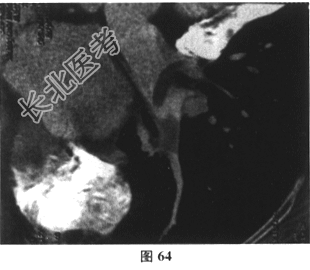

- 多项选择题3.[提示]入院后持续监测,生命体征平稳, 经对症治疗症状逐渐缓解。进一步检查,下肢深静脉多普勒超声: 右侧腘静脉、胫后静脉多发血栓形成。肺动脉CTA(图62~图65)示双肺动脉分支多发栓塞。冠脉CTA示冠脉多处钙化斑块,前降支中段轻度狭窄。BNP36.8pg/ml(正常0~100pg/ml)。TNI<0.05ng/ml(正常0~0.4ng/ml)。动脉血气分析: 氧分压63mmHg,二氧化碳分压28.7mmHg。